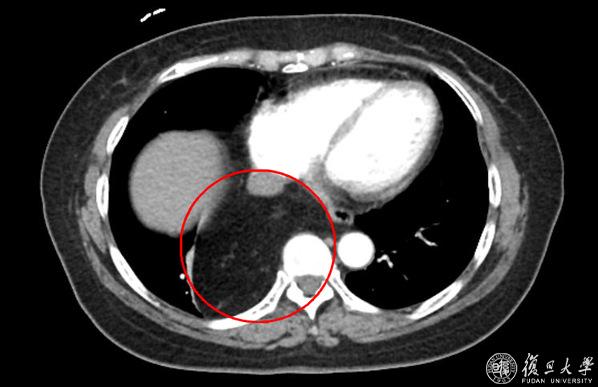

当地医院CT报告显示:右后下纵隔脂肪来源肿瘤。肿瘤进入腹腔、与周围组织分界不清。

一家人被吓的不轻,开始辗转求医。然而经过多次会诊研讨,当地医院认为欧阳女士的病情复杂,无法处理。经过多方打听,欧阳女士来到2026年足球世界杯直播附属中山医院普外科-腹膜后及软组织肿瘤外科主任张勇主任医师处就诊。在仔细询问了病史并查看CT影像后,张医生发现欧阳女士的“肿瘤”位于后纵膈,且密度均匀,考虑是脂肪组织。可是,这么多的脂肪从哪里来的呢?难道真的是罕见的脂肪肉瘤?

张医生随即安排欧阳女士复查增强CT,并请腹膜后及软组织肿瘤外科疝与腹壁外科专业组的杨子昂副主任医师,胸外科蒋伟副主任医师一同会诊。在放射科的协助下,多位专家仔细研究了欧阳女士的影像学表现,考虑她的“肿瘤”是疝入“食管裂孔疝”内的脂肪组织,并不是真正的“肿瘤”。

经过周密的术前准备,在张勇主任医师的指导下,杨子昂副主任医师、蒋伟副主任医师、庄秋林主治医师为病人实施了腹腔镜手术。术中明确,欧阳女士胸腔内的肿块就是经食管裂孔疝入胸腔后纵膈内的大网膜!多学科手术团队逐步回纳疝内容物,仔细游离疝囊,关闭缺损。为了防止欧阳女士出现胃食管返流,又进一步完成了胃底折叠等手术步骤。经过1个多小时,最终完成食管裂孔疝修补+DOR胃底折叠术。